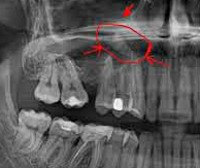

• Рентгенографию придаточных пазух носа. На рентгенограмме выявляется затемнение полости синуса и наличие горизонтального уровня жидкости. Для установления этиологии проводится рентгенография зубов с пораженной стороны.